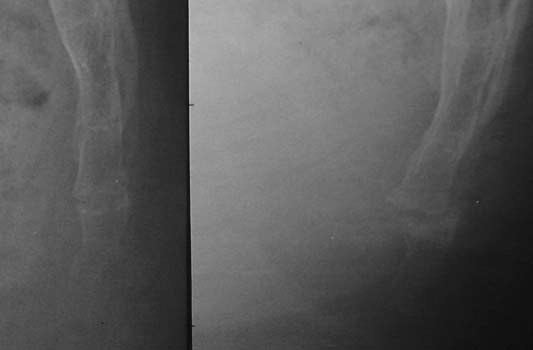

Case #10: Bad luck: two luxations at two different levels...

The sitting film is on the left. The story ended up rapidly at the

surgeon's office.